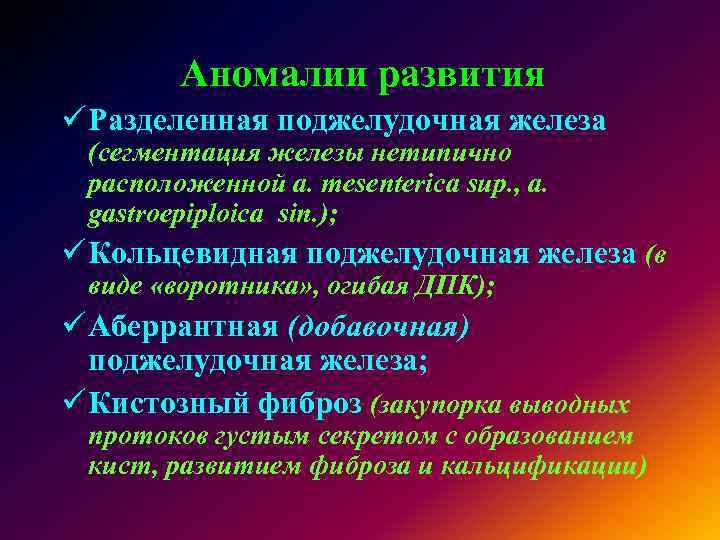

УЗИ диагностика кольцевидной поджелудочной железы: что важно знать

Раздел: Кадры перемен